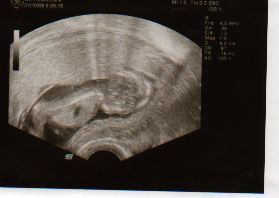

31.10.2008- vyšetření ve 13tt u MUDr. Čoupkové, vše v pořádku(12+4), termín porodu posunut na 13.5.2009